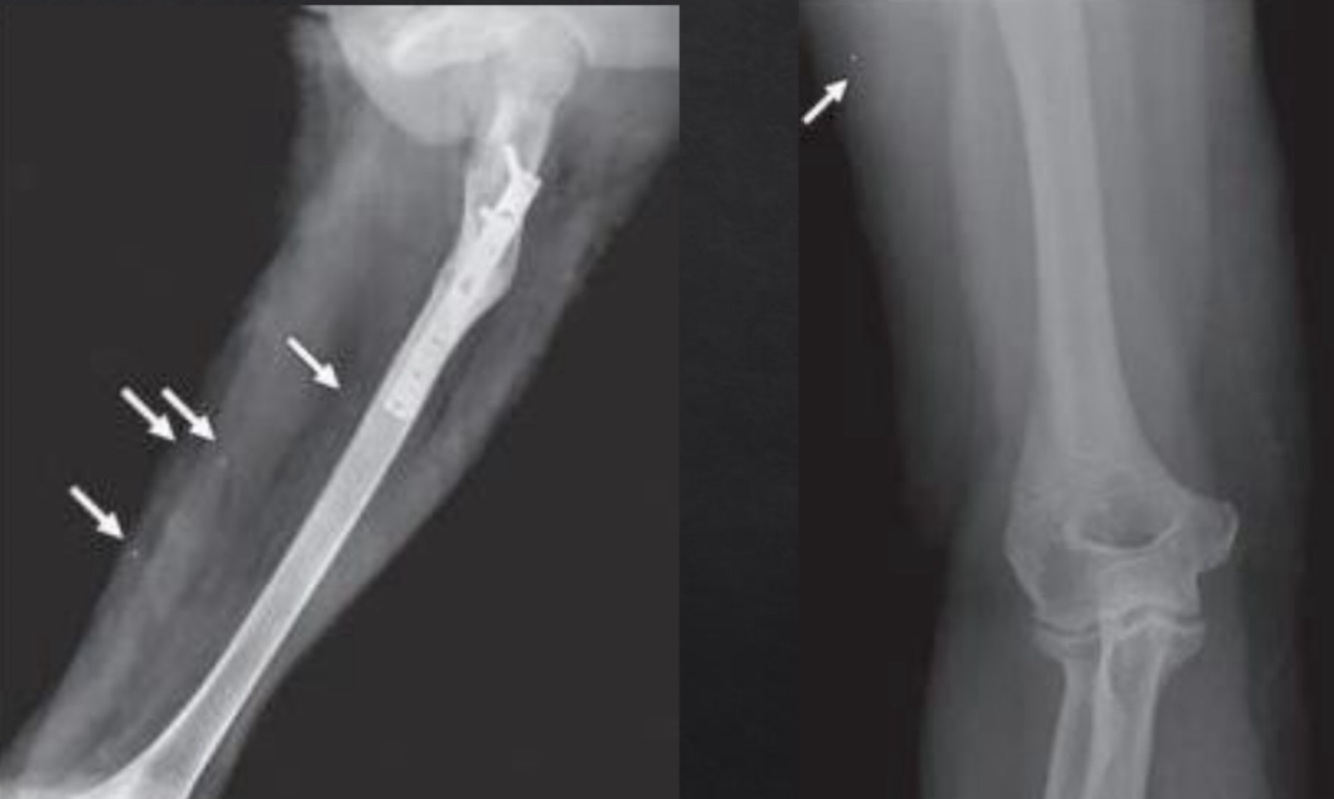

Foreign body: Bullet